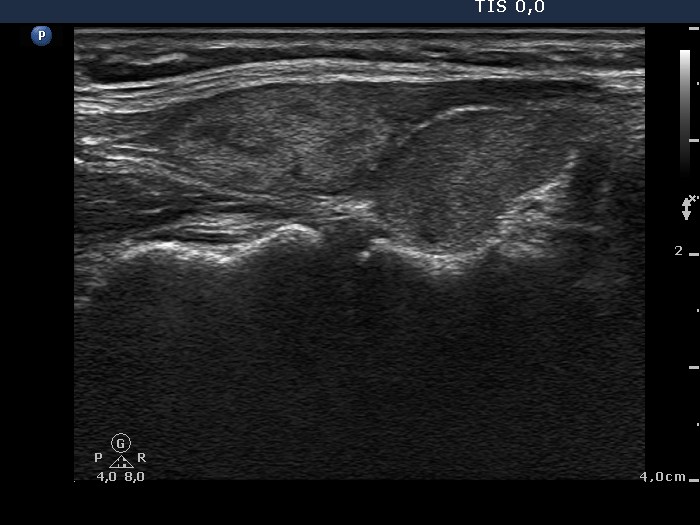

Ultrasonography: the thyroids were moderately hypoechogenic. There was an echonormal, inhomogeneous mass next to the upper pole of the right lobe. Muscle fibers were found between the thyroid and the hyperechogenic lesion. The latter displayed type 2 vascular pattern.